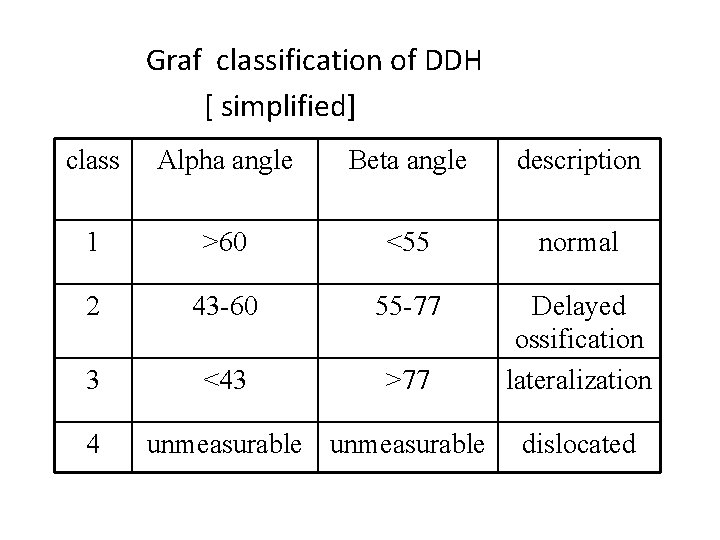

Developmental Dysplasia Of The Hip DDH Definition Dysplasia

Developmental Dysplasia Of The Hip DDH Definition Dysplasia

Developmental Dysplasia Of The Hip DDH Definition Dysplasia

Developmental Dysplasia Of The Hip DDH Definition Dysplasia

Developmental Dysplasia Of The Hip DDH Definition Dysplasia

Developmental Dysplasia Of The Hip DDH Definition Dysplasia

Developmental Dysplasia Of The Hip DDH Definition Dysplasia

Developmental Dysplasia Of The Hip DDH Definition Dysplasia